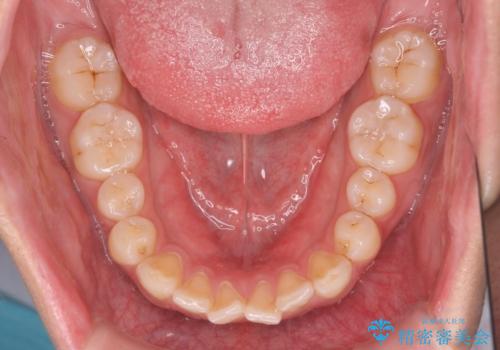

前歯が気になる。インビザラインライト

- 前歯が気になるとの事で来院。

矯正を希望されたが費用と時間を抑えたいとの事でインビザラインライトで矯正を行いました。(奥歯の位置関係はほぼ変えない)

前歯が綺麗に並び大変満足して頂けました。